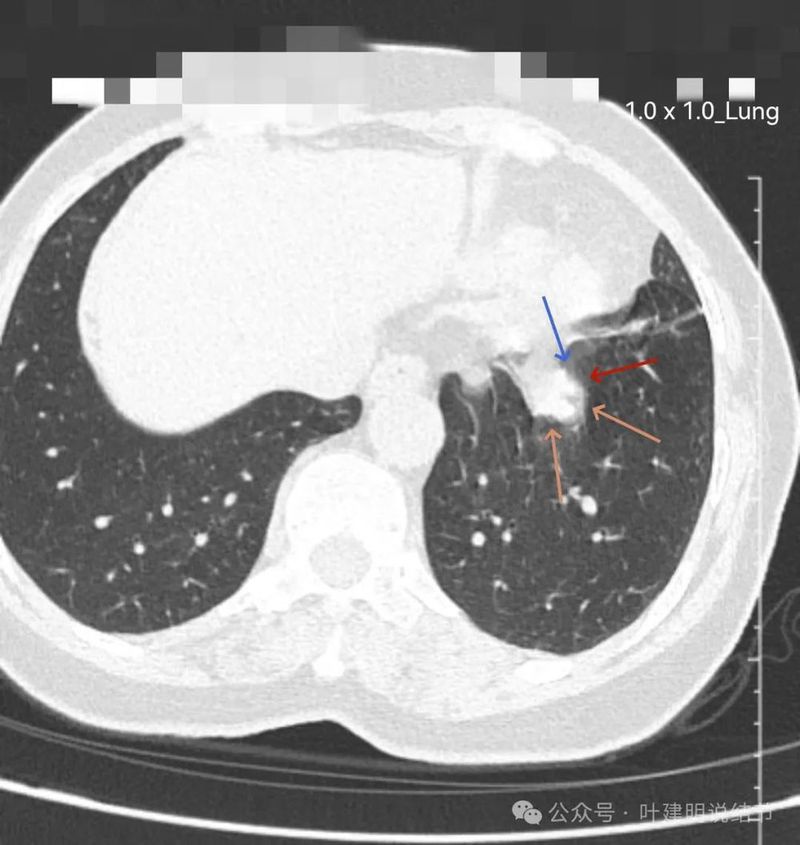

左下实性结节,明显有膨胀感,边缘虽然光滑,但给人感觉不舒服,恶性的可能性大些。

轴位病灶实性,分叶,膨胀!

病灶表面不平,有浅分叶,与膈肌之间有间隙。

与膈肌之间间隙明显,病灶实性,膨胀性明显,边缘相对较为光滑。

病灶浅分叶,膨胀性,周围有很淡的磨玻璃密度似的,这可能是检查时屏气屏得不太好的关系,不太符合混合磨玻璃结节的样子。

整体感觉较圆,膨胀性是明显的。膈肌有点被它顶过去的样子。

上图层面相对最大,感觉鼓鼓的。

两肺多发小结节,大部分是实性微小的,没有临床意义,只需随访;部分是淡而小的磨玻璃结节,也意义不大,能常规年度随访。主病灶则在左下叶近膈面处,此灶实性,有膨胀感,表面有浅分叶,但邻近膈肌与胸膜,未见明显胸膜牵拉,说明收缩力不明显。总体轮廓较清,没有卫星病灶,也无周围炎性渗出性或磨玻璃成分。此灶定要说良性或恶性,仍不能定。符合良性的是:边缘较为光滑,缺乏收缩力,未见血管征;符合恶性的是:有膨胀性与浅分叶,周围清晰不似普通炎性。但我们若换个角度来看问题:此灶若确实是恶性,那是实性的肺癌,随访是有风险的;若确实是良性,若予以单孔胸腔镜下局部楔形切除对肺功能影响并不大,手术风险也低,既能明确诊断又去除了病灶。也就是说:事实上恶性再随访存在风险,而事实上良性切了影响不大,手术的利弊权衡是利大于弊的(当然若确实是恶性,又做了手术,当然更是应该的)。所以我的意见:倾向恶性点,建议微创手术。如果对手术比较抗拒,也可适当口服抗炎治疗10-12天,之后间隔6-8周复查下增强CT或PET-CT(PET更有价值点)再决定也是可行的。意见供参考!